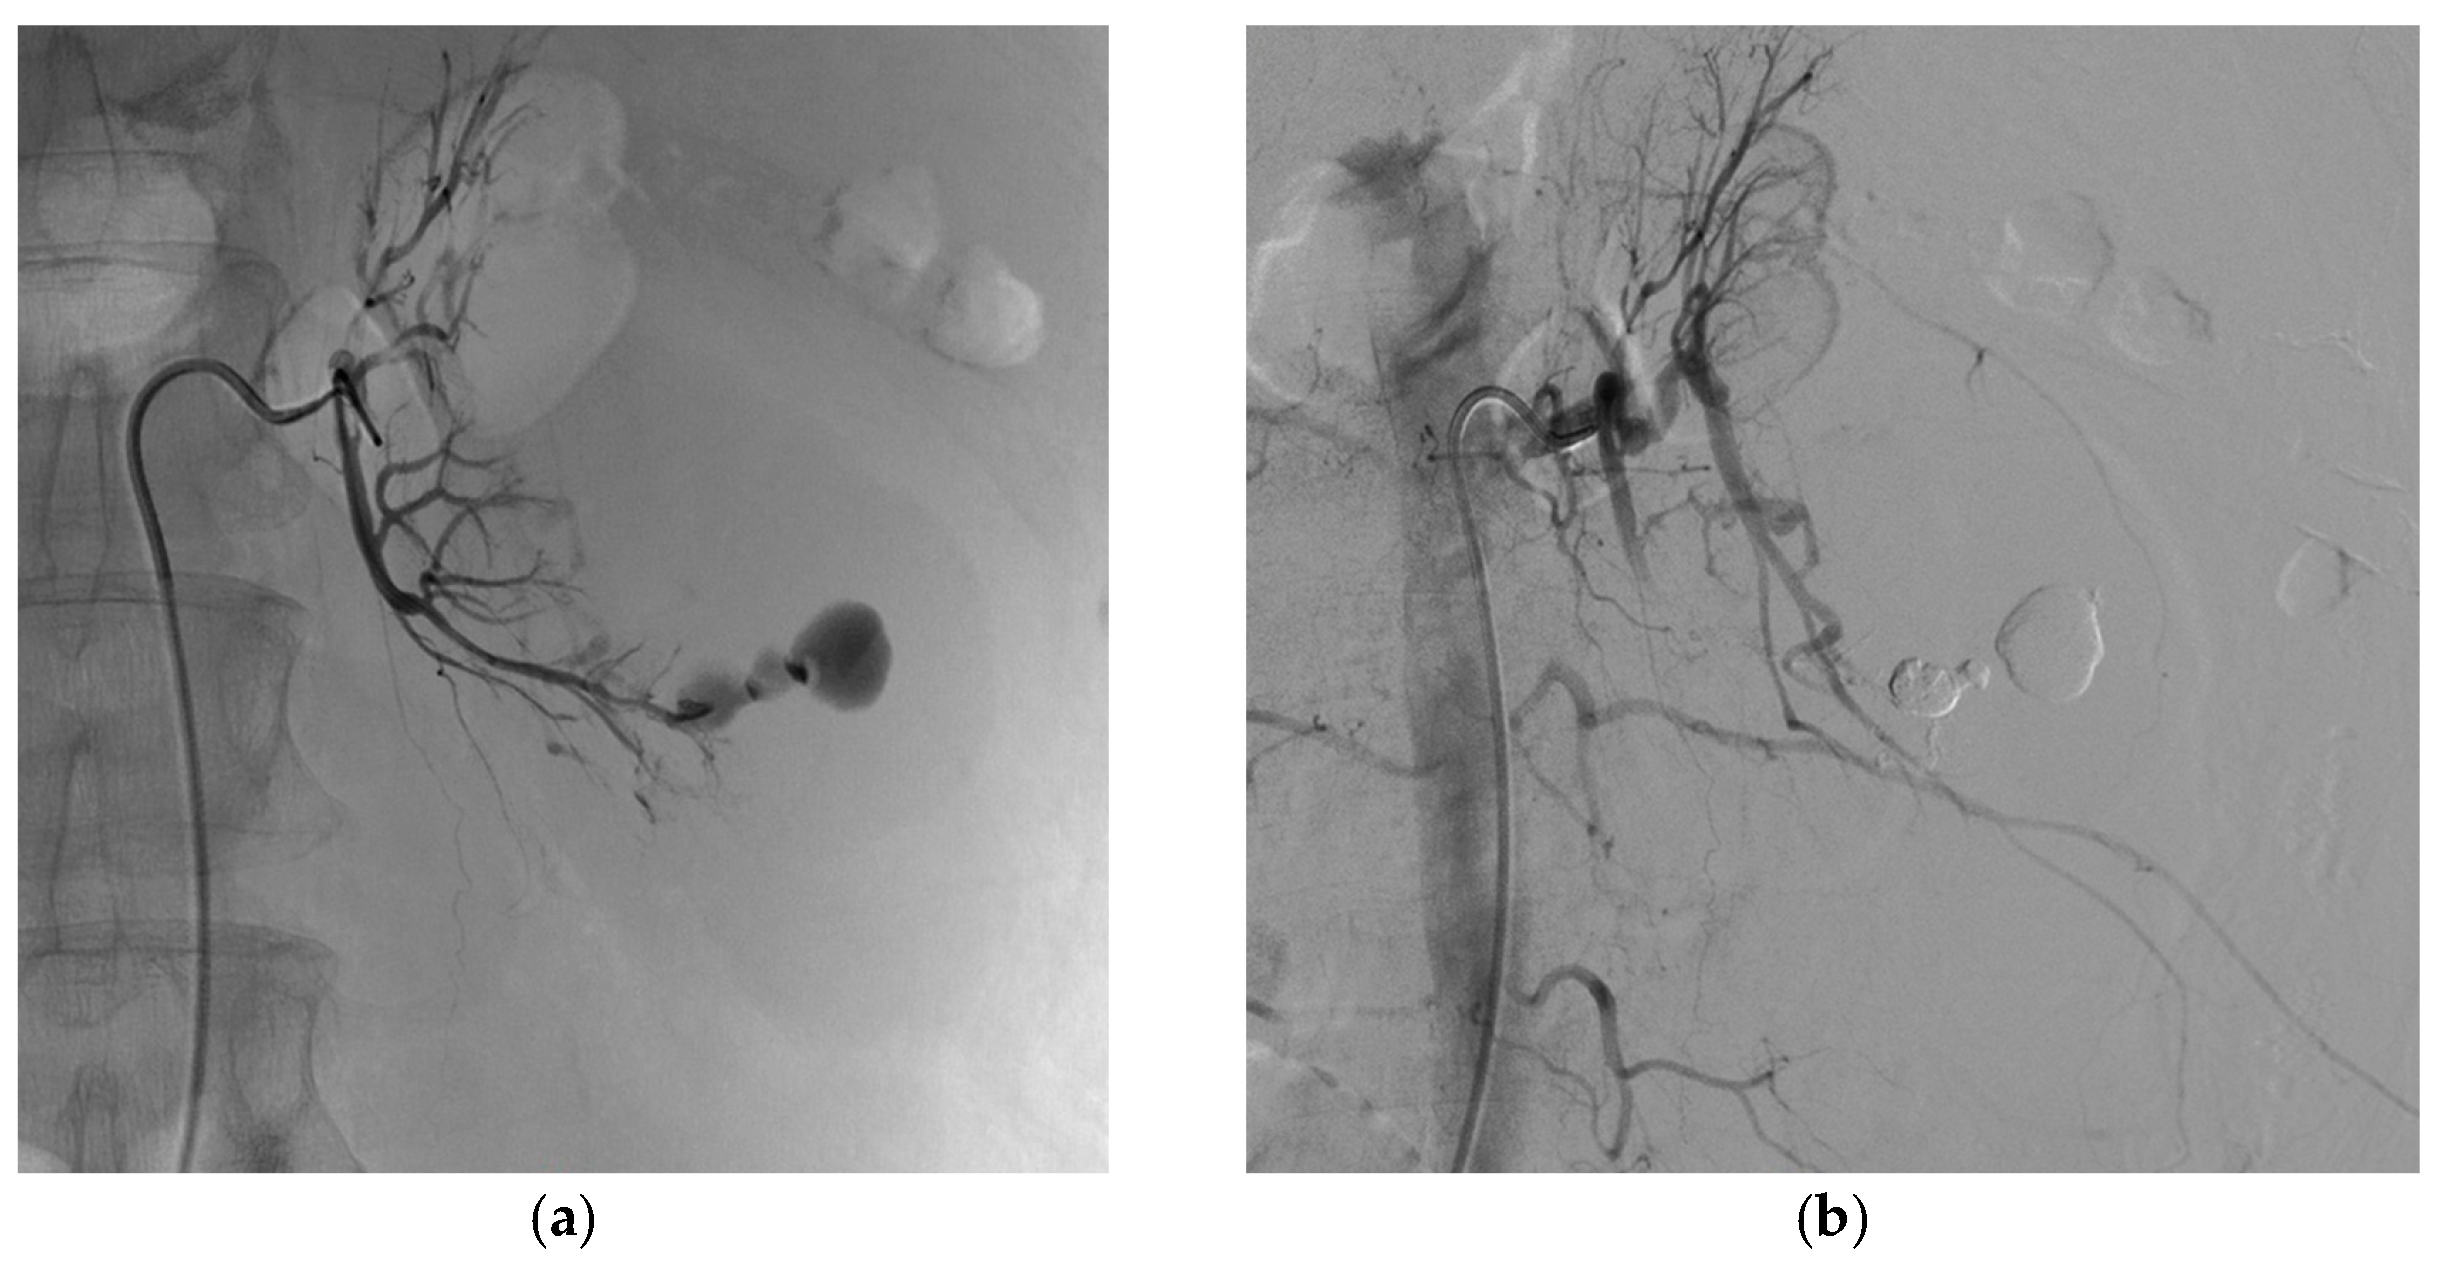

3.2. Endovascular Treatment

| Iatrogenic vascular lesion | |

| Number of renal false arterial aneurysms | 47 |

| Number of renal arteriovenous fistulas | 9 |

| Number of patients with both | 7 (28%) |

| Aneurysm size (mm) | 10.5 (±4.7) |

| Embolization technique | |

| Coils | 8 (32%) |

| Liquid embolic agent | 8 (6 Glubran2, 1 Onyx, 1 Gelatispon) (32%) |

| Coils and liquid embolic agent | 9 (36%) |

| Technical success at first attempt | 24 (96%) |

| Technical success at first or second attempt | 25 (100%) |

| Clinical success, one attempt | 24 (96%) |

| Clinical success, one or two attempts | 25 (100%) |